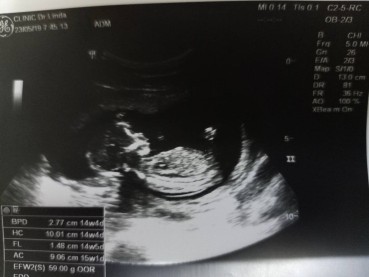

รูปตอน14weekค่ะ ตอนนี้ 18weekแล้วค่ะ